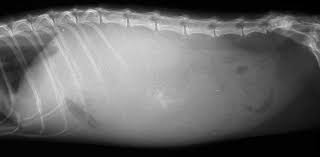

염분 탓인지 아니면 종양이 커진 탓인지. 복수가 찬것 같이 배가 엄청 커져서

일단 고양이 경우에.. 가장 좋은 방법은 복수 천자라 합니다

복수 천자는 복수에 주사기로 바늘을 찔러서 복강내 고여있는 물을 빼내는 방법 인데

겉으로 볼땐 엄청 위험해 보이나 단순히 바늘로 물을 빼는 방법이라 비교적 쉽고 간단 하며

비용이 크게 발생 되지 않고, 고양이에게 치명적이지도 않습니다

복수 천자 비용은 5만원이 안나오기 때문에 비교적 저렴하지만 문제는 초음파를 통해서

(초진 비용이 발생) 복수가 찼는지 여부 와. 종양이 복수를 가리고 있는지 여부를 알아야 복수천자가

가능합니다. 그러니까 종양에 덮혀 복수가 안쪽으로 있는 경우, 주사바늘이 들어가지 못해 복수 천자

불가능할수도 있고 복수가 찬것이 아닐수도 있기 때문에 초음파로, 확인을 먼저 해야 하는 것이지요